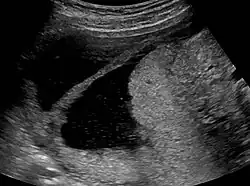

The history of a pregnancy event followed by a D&C leading to secondary amenorrhea or hypomenorrhea is typical. Hysteroscopy is the gold standard for diagnosis.[18] Imaging by sonohysterography or hysterosalpingography will reveal the extent of the scar formation. Ultrasound is not a reliable method of diagnosing Asherman's Syndrome. Hormone studies show normal levels consistent with reproductive function.